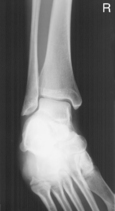

This is a frontal view of the entire ankle mortise and generally should not be a substitute for the routine AP or 45° oblique ankle.